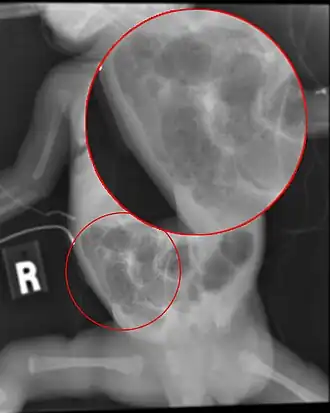

Les radiographies de l'abdomen sans préparation montrent les signes d'iléus, de distension intestinale, de pneumatose intestinale et, ou portale — avec des clartés gazeuses soulignant les silhouettes du foie et, ou de la rate[10] — voire un pneumopéritoine[11]. Les critères radiocliniques de gravité suivants ont été établis au cours des années 1970 :

| Stade | Signes généraux | Signes intestinaux | Signes radiologiques | |

|---|---|---|---|---|

| ENN douteuse | Ia : suspectée | * apathie ou agitation ; * apnées-brachycardies ; * dysrégulation thermique ; ± CRP | * volumes des résidus gastriques ; * vomissements ; * météorisme abdominal indolore et non silencieux ; ± modification des selles, pas de sang macroscopique | Aspect normal ou dilatation des anses intestinales, iléus modéré (anse fixée) |

| " | Ib : douteuse | idem ci-dessus | idem ci-dessus + sang rouge dans les selles | idem ci-dessus |

| ENN prouvée | II : de gravité faible à moyenne | idem ci-dessus ; ± acidose métabolique ; ± thrombopénie | idem ci-dessus ; + météorisme silencieux ; ± résidus verts ; ± défense ; ± plastron FID ; ± paroi inflammatoire | * Dilatation intestinale ; + pneumatose intestinale et, ou portale ; ± épanchement péritonéal |

| " | III : grave | idem ci-dessus ; ± hypotension, oligurie, troubles hydroélectrolytiques ; ± acidose mixte ; ± neutropénie ; ± CIVD ; ± SDRA | idem ci-dessus ; + météorisme volumineux, douloureux avec contracture | idem ci-dessus ; ± pneumopéritoine de la grande cavité ou localisée ; ± épanchement péritonéal franc |